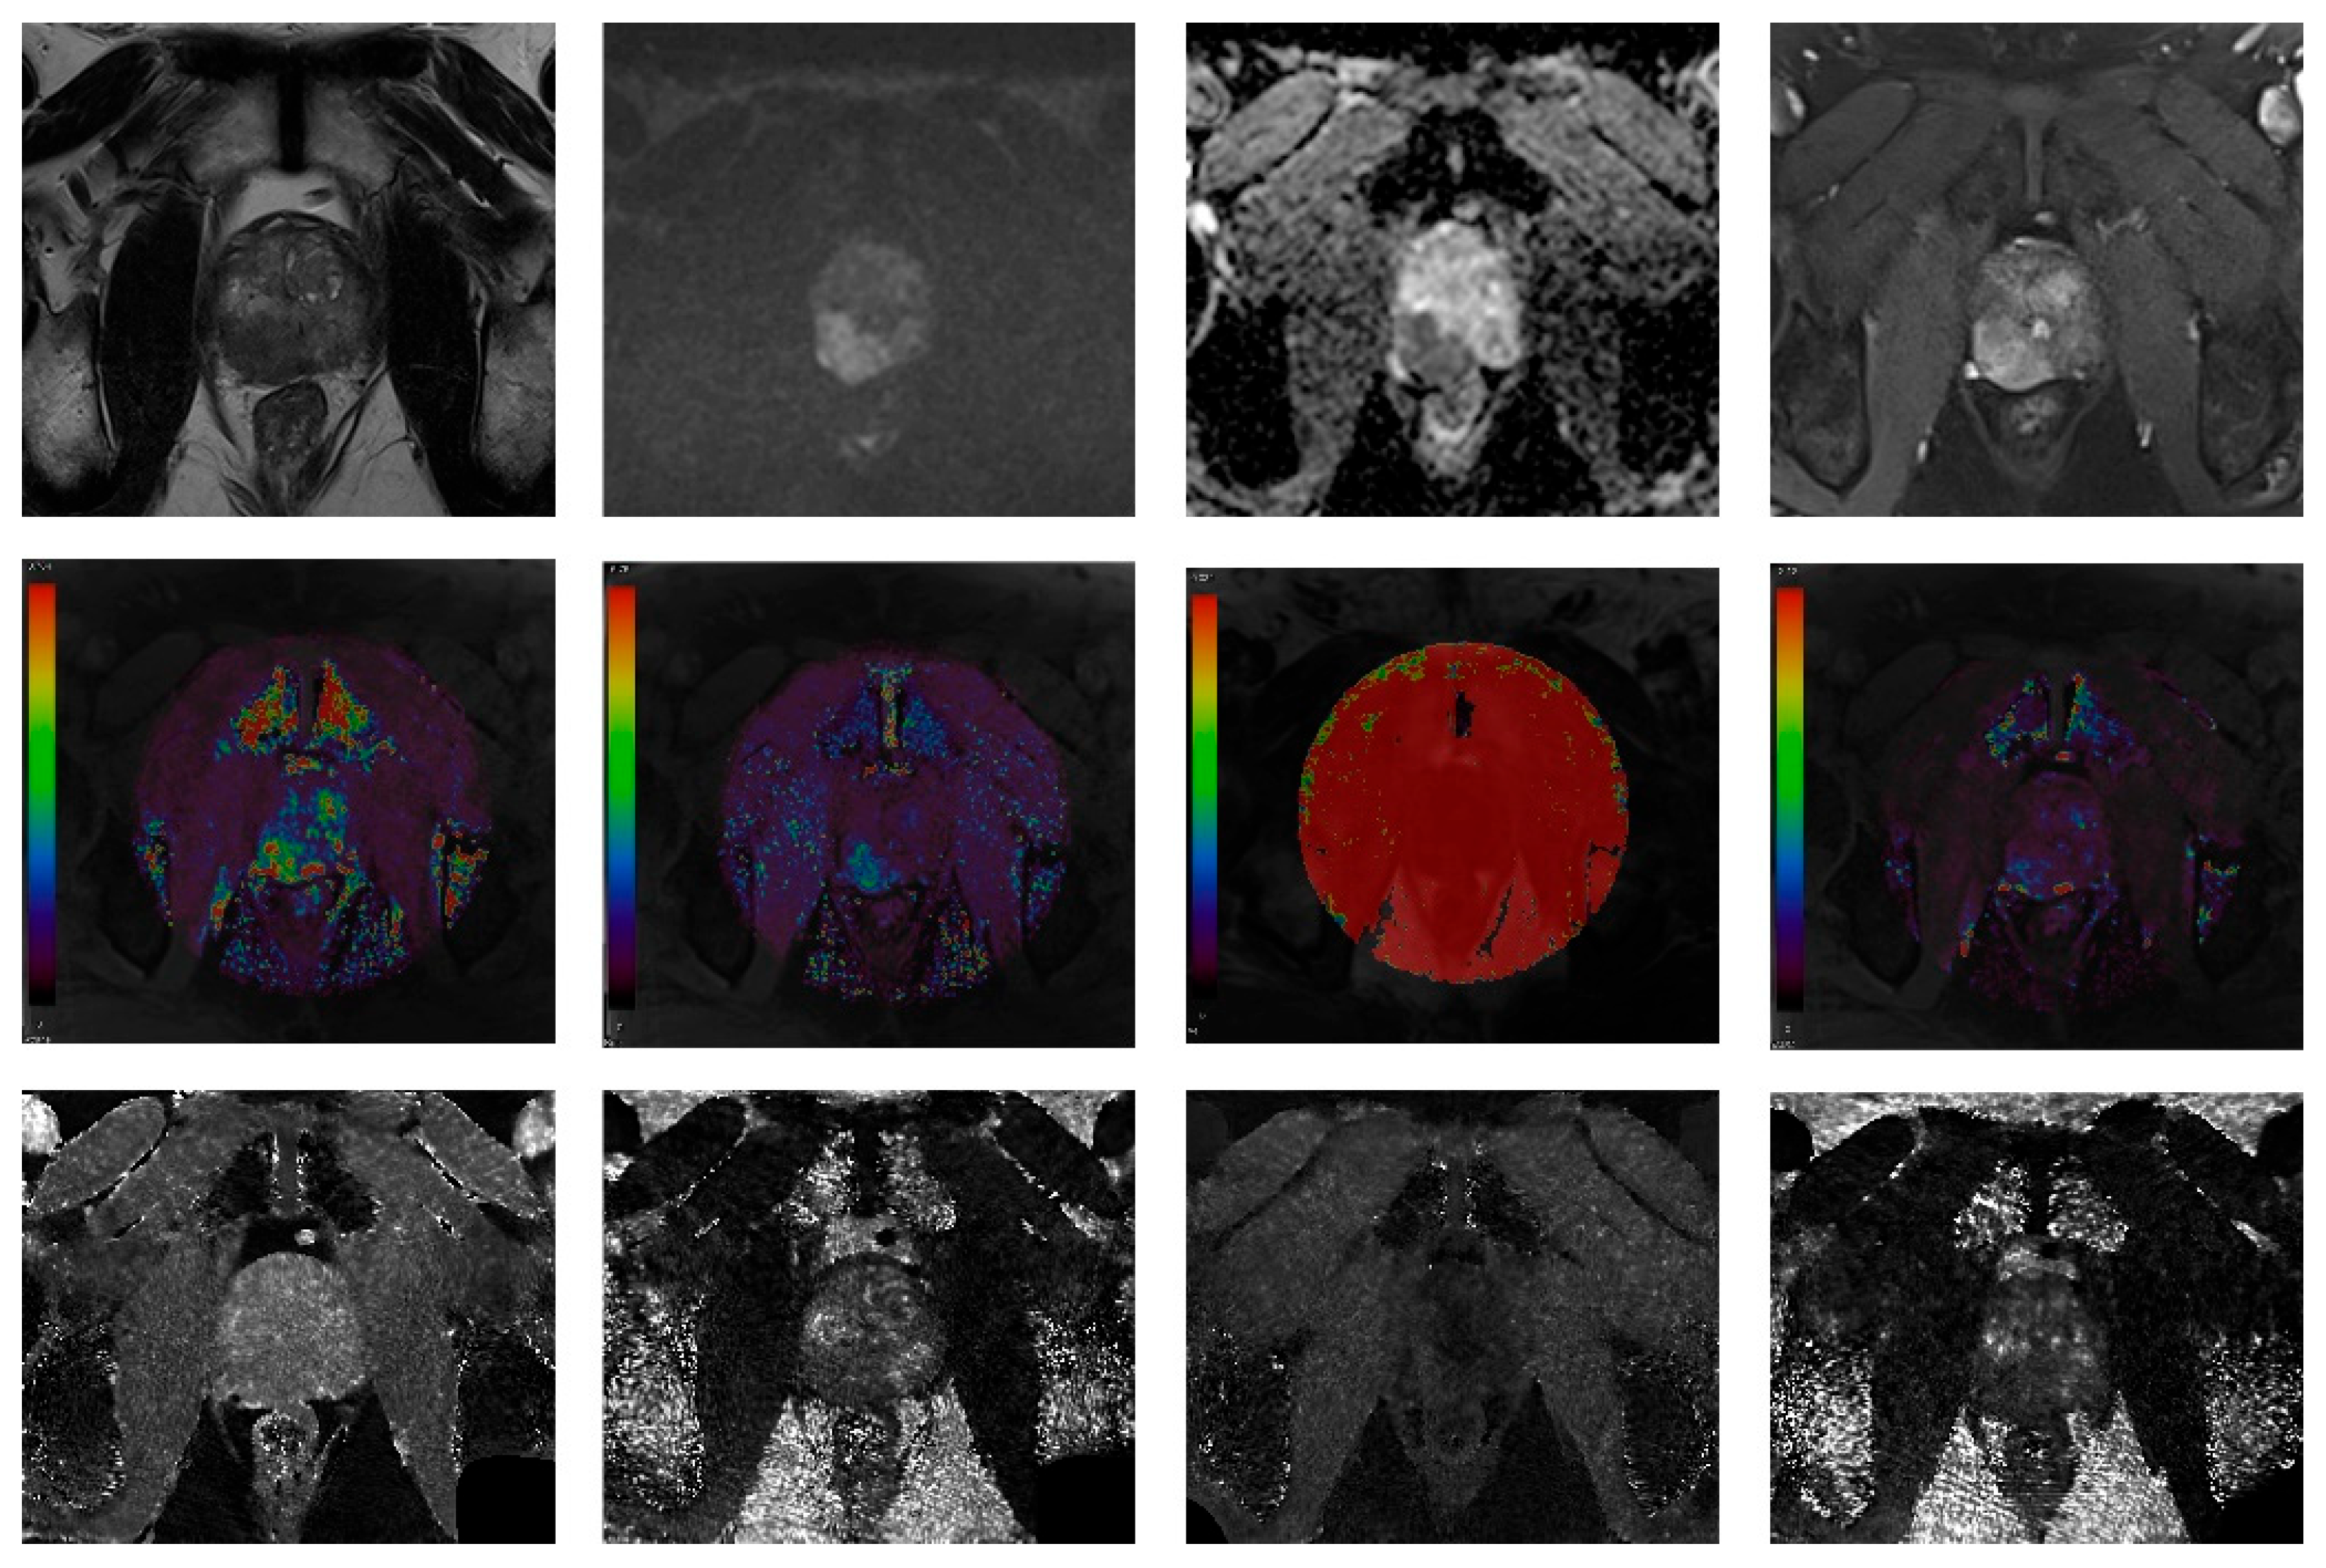

Rough information about the location of the most severe prostate focal lesion (right or left, peripheral zone or transition zone) that was reported in the clinical MRI report was provided to the radiologists. However, they were unaware of the biopsy results. They independently drew a region-of-interest (ROI) covering the abnormal focal lesion on the axial image that contained the largest diameter of the lesion. The average values of the parameters were extracted from the ROIs. The images of a representative case are presented in Figure 2.

A 2.5 cm hypointense bulging lesion was detected in the right peripheral zone on the T2-weighted image (T2WI) with a high signal intensity on the B = 1500 mm2/s diffusion-weighted image (DWI), a low value on the apparent diffusion coefficient (ADC) map, and early enhancement on the dynamic contrast-enhanced (DCE) MRI (T2WI, DWI, ADC map and DCE MRI in order from left, top row). The DCE parametric maps (Ktrans, Kep, Ve, and iAUC in order, middle row) and MRF maps (nonenhanced [NE] T1, NE T2, contrast-enhanced [CE] T1, and CE T2 maps in order, bottom row) are presented.

Figure 2. A 66-year-old patient with elevated prostate-specific antigen (15.5 ng/mL).